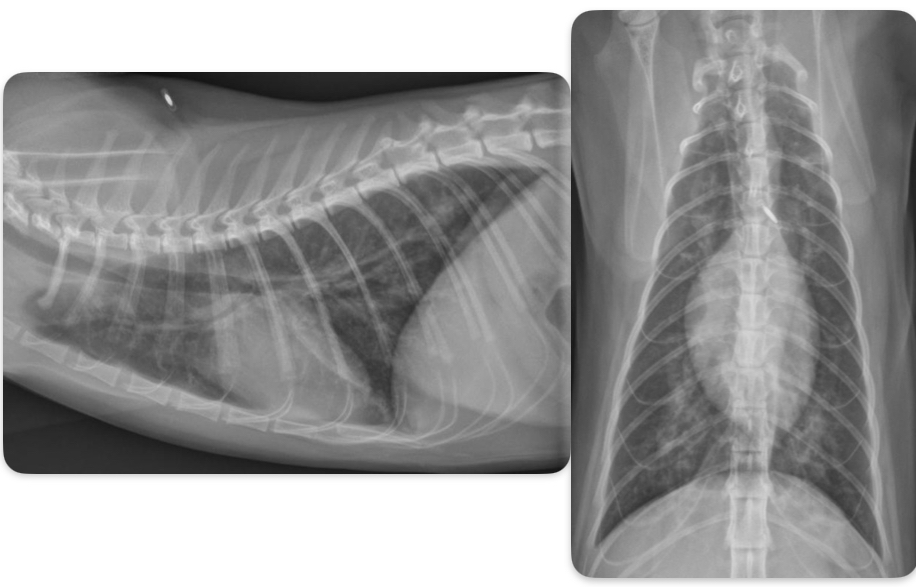

Roentgen signs of DCM

-Generalized cardiomegaly

± LHF > RHF or biventricular heart failure

-unstructured interstitial to alveolar in cd.dorsal